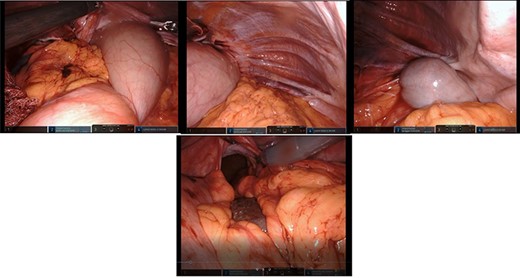

After mobilization of the left liver lobe, visualization of the hiatus was achieved. A two silk suture was placed through the avascular hepatogastric ligament and outside the patient’s anterior abdomen with an extracorporeal knot in order to assure atraumatic elevation-retraction of the liver. Space was created in the surgical field due to the absence of a retracting surgical instrument within the abdominal cavity. The hernia’s sac was then dissected with use of energy device and bipolar cautery with minimal traumatic tissue handling; the herniated stomach, transverse and left colon, omentum and finally spleen were dissected free (Fig. 2). Due to the atypical clinical symptomatology as well as increased PLT, the suspicion of chronic ischemia of the herniated organs was raised. ICG was administered to assess the patency of blood supply in the herniated organs and specially to the spleen; blood supply was excellent and as a result, no further resections were needed (Fig. 3). An 8- × 4-cm posterolateral diaphragmatic defect was revealed; the defect was repaired with the use of ProGrip mesh and was supported by a continuous V-loc suture for fixation. The patient resuscitated from anesthesia in great condition and returned to the ward, with an uneventful course. A post-operative upper GI fluoroscopy was conducted at the second post-operative day (POD), and oral diet was commenced (Fig. 4).

The use of intraoperative ICG and the use of Firefly camera to assess blood supply and viability of the spleen.

The use of ICG while utilizing the Firefly camera of the DaVinci Xi Robotic System is another innovation used in this case. It is the only case reported of leftside Bochdalek hernia in international literature, which utilizes such contrast media intraoperatively. Assessment of blood supply with a harmless substance at the time of operation is an undeniable weapon in the surgeon’s arsenal in order to provide the patient with the optimal treatment without inadvertently assuming false blood supply of the herniated organs. The phenomenon of ischemia in such hernias has been reported and further anatomical dissections were required [10, 14, 15]. Macroscopic alteration of blood supply could be absent at time of operation, so intraoperative ICG green application readily evaluates such cases.